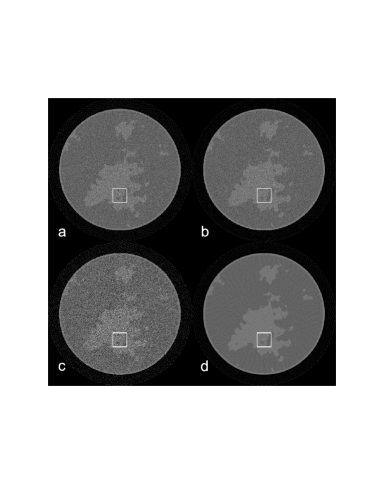

In order to evaluate we note that

| (25) |

Therefore, recalling Eqn. 14 and applying the chain rule,

| (26) |